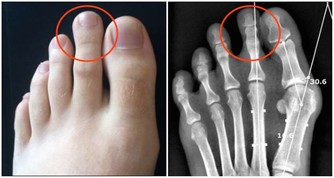

不正確的運動方式或飲食計劃可能導致效果不佳,甚至損害健康。例如,過度節食或運動過量會對身體造成負面影響,讓人感覺健康生活變得「辛苦且無效」。